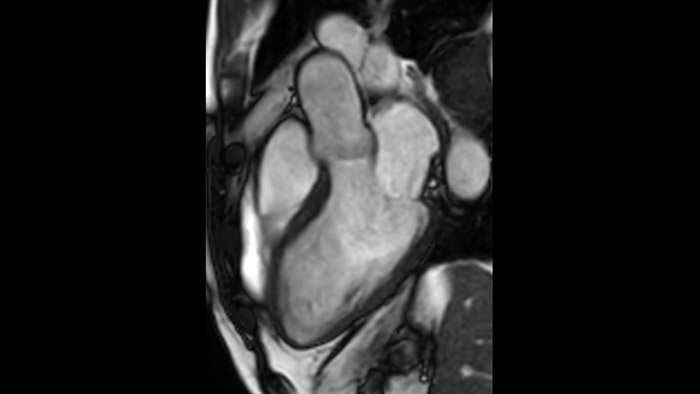

La utilidad diagnóstica y pronóstica de la RM cardíaca está aumentando. Evaluar la anatomía y función del corazón mediante adquisiciones cinematográficas, adquirir información sobre perfusión y viabilidad del tejido cardíaco, visualizar posibles edemas con secuencia de sangre negra, acceder e incluso cuantificar la caracterización tisular con CardiacQuant.